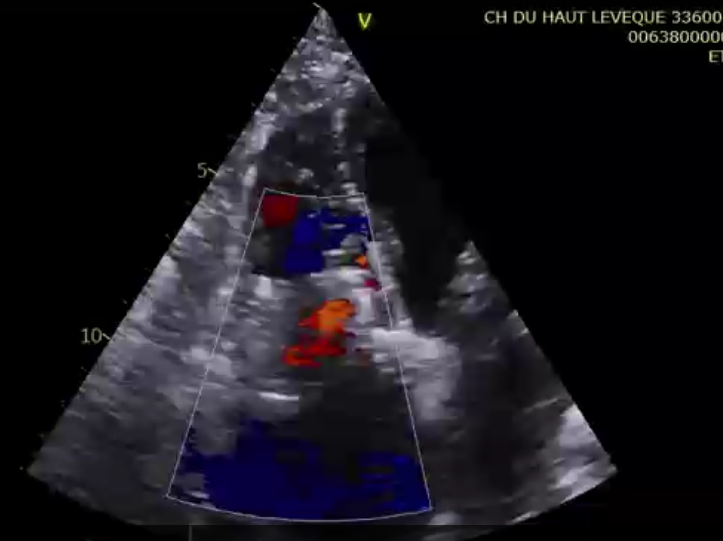

術后超聲提示微量瓣周漏